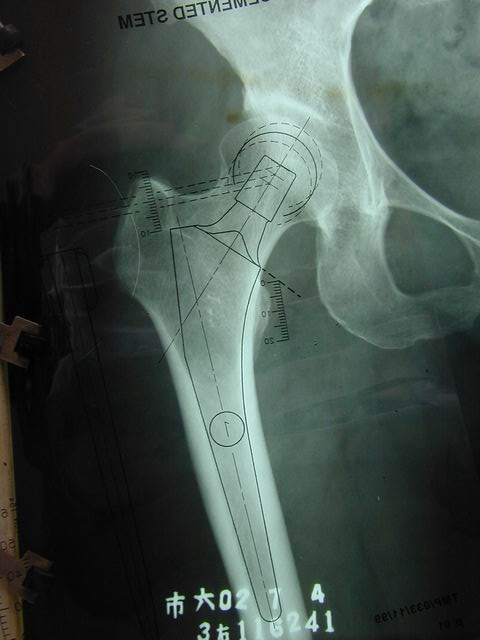

确定股骨颈截骨线对侧髋关节正常,可以对侧为参照

-选择合适的颈长(一般将设计的颈长定为中颈,以保留适当的调整余地)

-将假体股骨头的旋转中心与髋臼假体的旋转中心相吻合

-定出截骨高度(可以小粗隆为参照)

-镜像确定在患侧的截骨高度

确定股骨假体的大小1、在截骨位置正确选择股骨假体的尺寸2、需考虑股骨在侧位片上的匹配程度